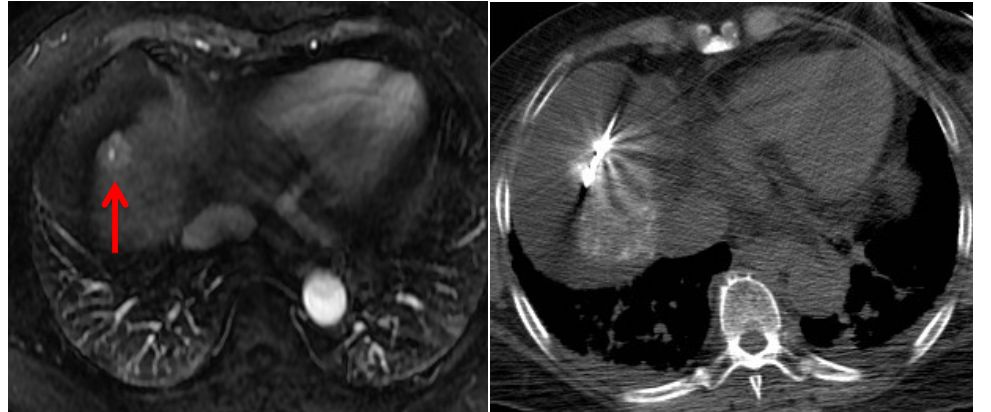

由于肝脏特殊的生理解剖,临近危险器官的特殊部位以及影像显示不清的肝肿瘤,一直是影像引导下经皮消融治疗的难点或“禁区”。 近日,我院放射科介入病房邵海波教授、田玉龙主治医等在麻醉科的大力配合下,为一名复杂的肝癌患者进行了影像引导下的经皮微波消融治疗。手术仅历时1.5小时,术后3天患者即顺利出院。 患者为62岁女性,半年前诊断为原发性肝癌,为肝左叶单发病灶,曾行经导管肝动脉化疗栓塞和微波消融治疗,术后病灶完全灭活。本次入院MRI检查发现新发肿瘤,肝内共有4个活性病灶,分别位于心缘旁、膈顶、胆囊旁等“危险部位”,血供较差,TACE治疗控制不佳,经详细讨论,决定采用经皮微波消融治疗。由于病变位置特殊,加之平扫CT或超声均不能清晰的显示全部病灶,大大增加了消融治疗的难度和风险。术中,治疗团队采用腹水隔离、CT/超声双引导进针监测、解剖标记定位、低功率间断消融等多种辅助手段相结合,对全部4处病灶进行了安全、精准的微波消融治疗,手术历时1.5小时,术后3天患者顺利出院。 图1. 临近心脏的膈顶部病灶,水隔离保护下消融 图2. 临近包膜的膈顶部病灶,水隔离保护消融 图3. 紧邻胆囊病灶,超声引导和监测下低功率间断消融 图4. CT和超声均显示不清的病灶,采用CT引导解剖标记定位消融 图5.肿瘤消融治疗是指利用消融治疗针穿刺肝肿瘤,针尖能够产生电磁波而使周围组织升温至80度以上的高温,从而杀灭肿瘤。 图6.危险部位肿瘤是指当肿瘤靠近膈顶、心脏、胃、肠管、胆囊、以及肝门部等部位时,对肿瘤进行消融就容易损伤相应的器官,引起并发症。因此这些部位的肿瘤称为危险部位肿瘤。 此病例癌症病灶位于膈顶部、心脏旁、胆囊旁、肝门部、大血管附近,肝边缘近胃肠道、外凸近腹壁,治疗难度大,技术复杂、成功率低、风险高。介入病房开展水隔离技术、胆管冷却技术、术中引流技术、造影增强定位技术、解剖标记定位技术、复合影像导航穿刺和监视技术等新技术对危险部位和复杂病灶进行成功的经皮消融治疗,几乎做到肝脏肿瘤消融无禁区、无死角。 近年来,影像引导下经皮微波消融治疗已成为肝癌/肝转移癌、肺癌、肾癌等实体肿瘤最为有效的微创治疗手段之一,具有创伤小、恢复快、疗效确切、可重复治疗等优点。据统计,2018年,放射科介入病房利用各种辅助技术处理复杂或高危部位肿瘤41例,疗效显著且无并发症发生,与前期未应用辅助技术的病例相比,完全消融的比率显著提高(93.5% vs.78.5%),不良反应发生率显著降低。 我院放射科介入病房自2004年开始开展影像引导下肝癌的射频/微波消融治疗,在放射科副主任苏洪英教授的领导下,不断突破技术难点,治疗水平逐年提高。科室选派技术骨干到国外学习先进技术,其中本例手术的术者邵海波教授就是在我院中青年骨干培训计划的支持下,在哈佛医学院/麻省总医院进行了为期近2年的消融治疗培训和研究后,回国将所学更好地应用于临床。目前,科室在影像引导下经皮肝肿瘤微波消融领域处于国内领先水平。